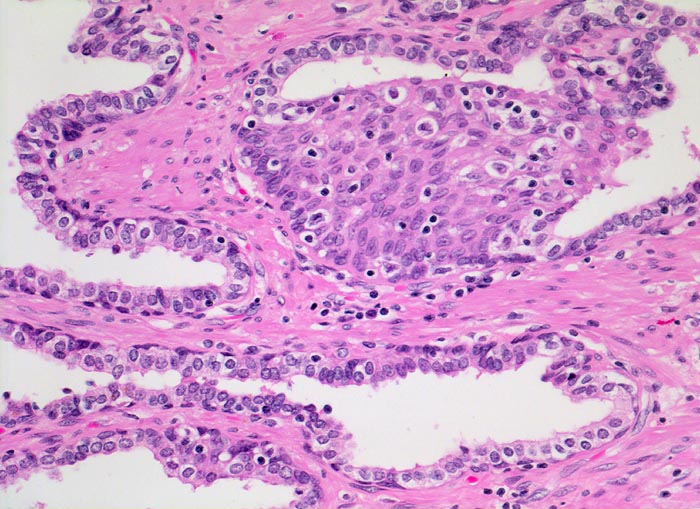

• Knotiges Parenchym.

• Organoid angeordnete, teils dilatierte grosse Drüsen eingebettet in ebenfalls vermehrtes fibroleiomyomatöses Stroma.

• Drüsen ausgekleidet von hochprismatischen sekretorischen Zellen (innen) mit unscheinbaren Nukleolen und durchgehender flacher Basalzellschicht (aussen).

• Konzentrisch geschichtetes hypereosinophiles Sekret in einigen Drüsenlumina (Corpora amylacea).

• Herdförmig geringes chronisches Entzündungsinfiltrat.